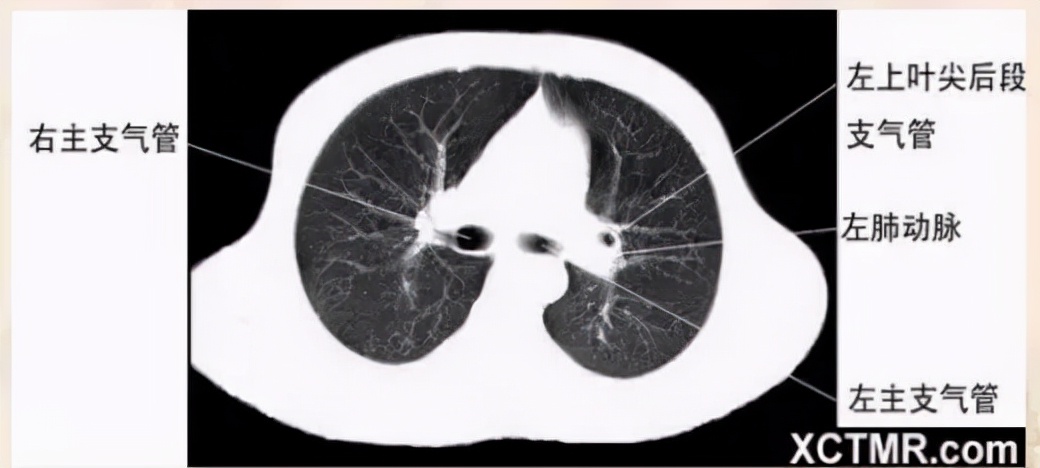

左主支气管层面